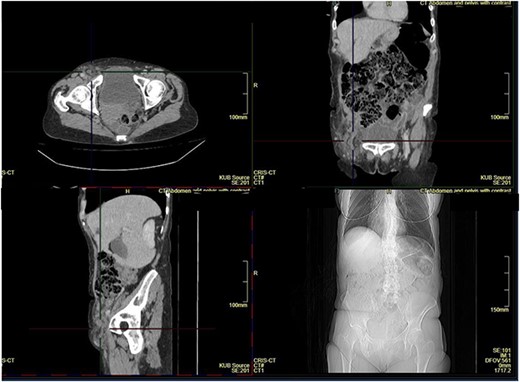

We report the case of a 66-year-old female who presented with a short history of sudden onset and worsening pain in the right groin. No symptoms suggestive of bowel obstruction were present. Previous history included an anterior resection, incisional hernia repair and thyroidectomy. On examination, there was a partially reducible, tender and palpable mass. Computed tomography (CT) scan of the abdomen pelvis was performed, which revealed a right femoral hernia and reported as containing incarcerated bowel loops (Fig. 1).